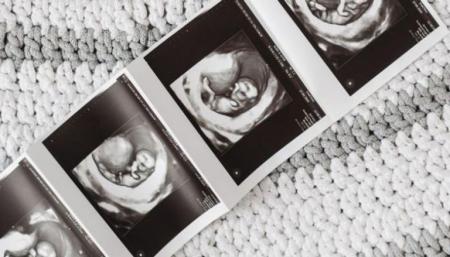

وبالفعل، حلل الباحثون بيانات تم جمعها في الفترة ما بين عامي 2018 إلى 2021 من 754 زوجًا من الأمهات والأجنة؛ فخلال الأشهر الثلاثة الأخيرة من الحمل، خضعت المشاركات لتصوير بالموجات فوق الصوتية عبر المهبل.

ويجدر بالذكر هنا أنّ هذا النوع من التصوير متخصص وعبره يمكن تحليل شكل دماغ الجنين وبنيته.